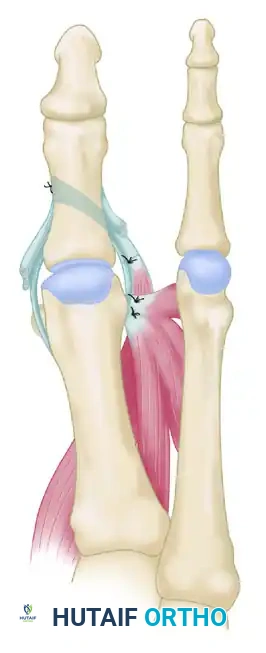

- Lateral Reconstruction: The adductor hallucis and flexor hallucis brevis conjoined tendon (if present) is mobilized, moved proximally, and sutured securely into the lateral aspect of the first metatarsal head, dorsal to the newly transferred abductor hallucis tendon.

- Fixation: The transferred abductor hallucis is sutured to the soft tissues medially under appropriate tension to maintain the hallux in a neutral to slight valgus alignment.

FIGURE 81-81C: Final construct showing the suturing of the abductor hallucis (lengthened by tendon graft if necessary) into the base of the proximal phalanx, alongside the repositioning of the conjoined tendon.